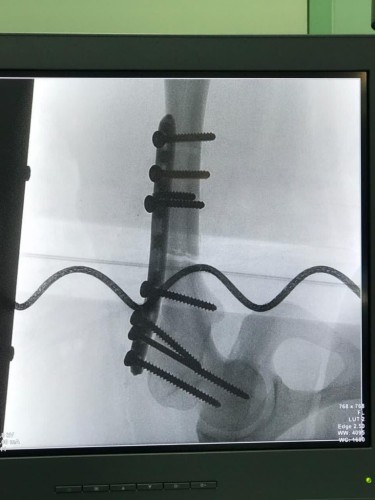

وكذلك تثبيت الكسور عند المصابين بإستخدام سيخ تيتانيوم نخاعي متشابك في حالة، واستخدام شريحة تيتانيوم متشابكة في الحالة الأخرى ، وذلك دون حدوث مضاعفات قبل أو بعد العملية، وتم خروج المريضين وهما يتمتعان بتلاشي الألم ونطاق حركة وظيفي والتمكن من الحركة باستخدام وسائل مساعدة.